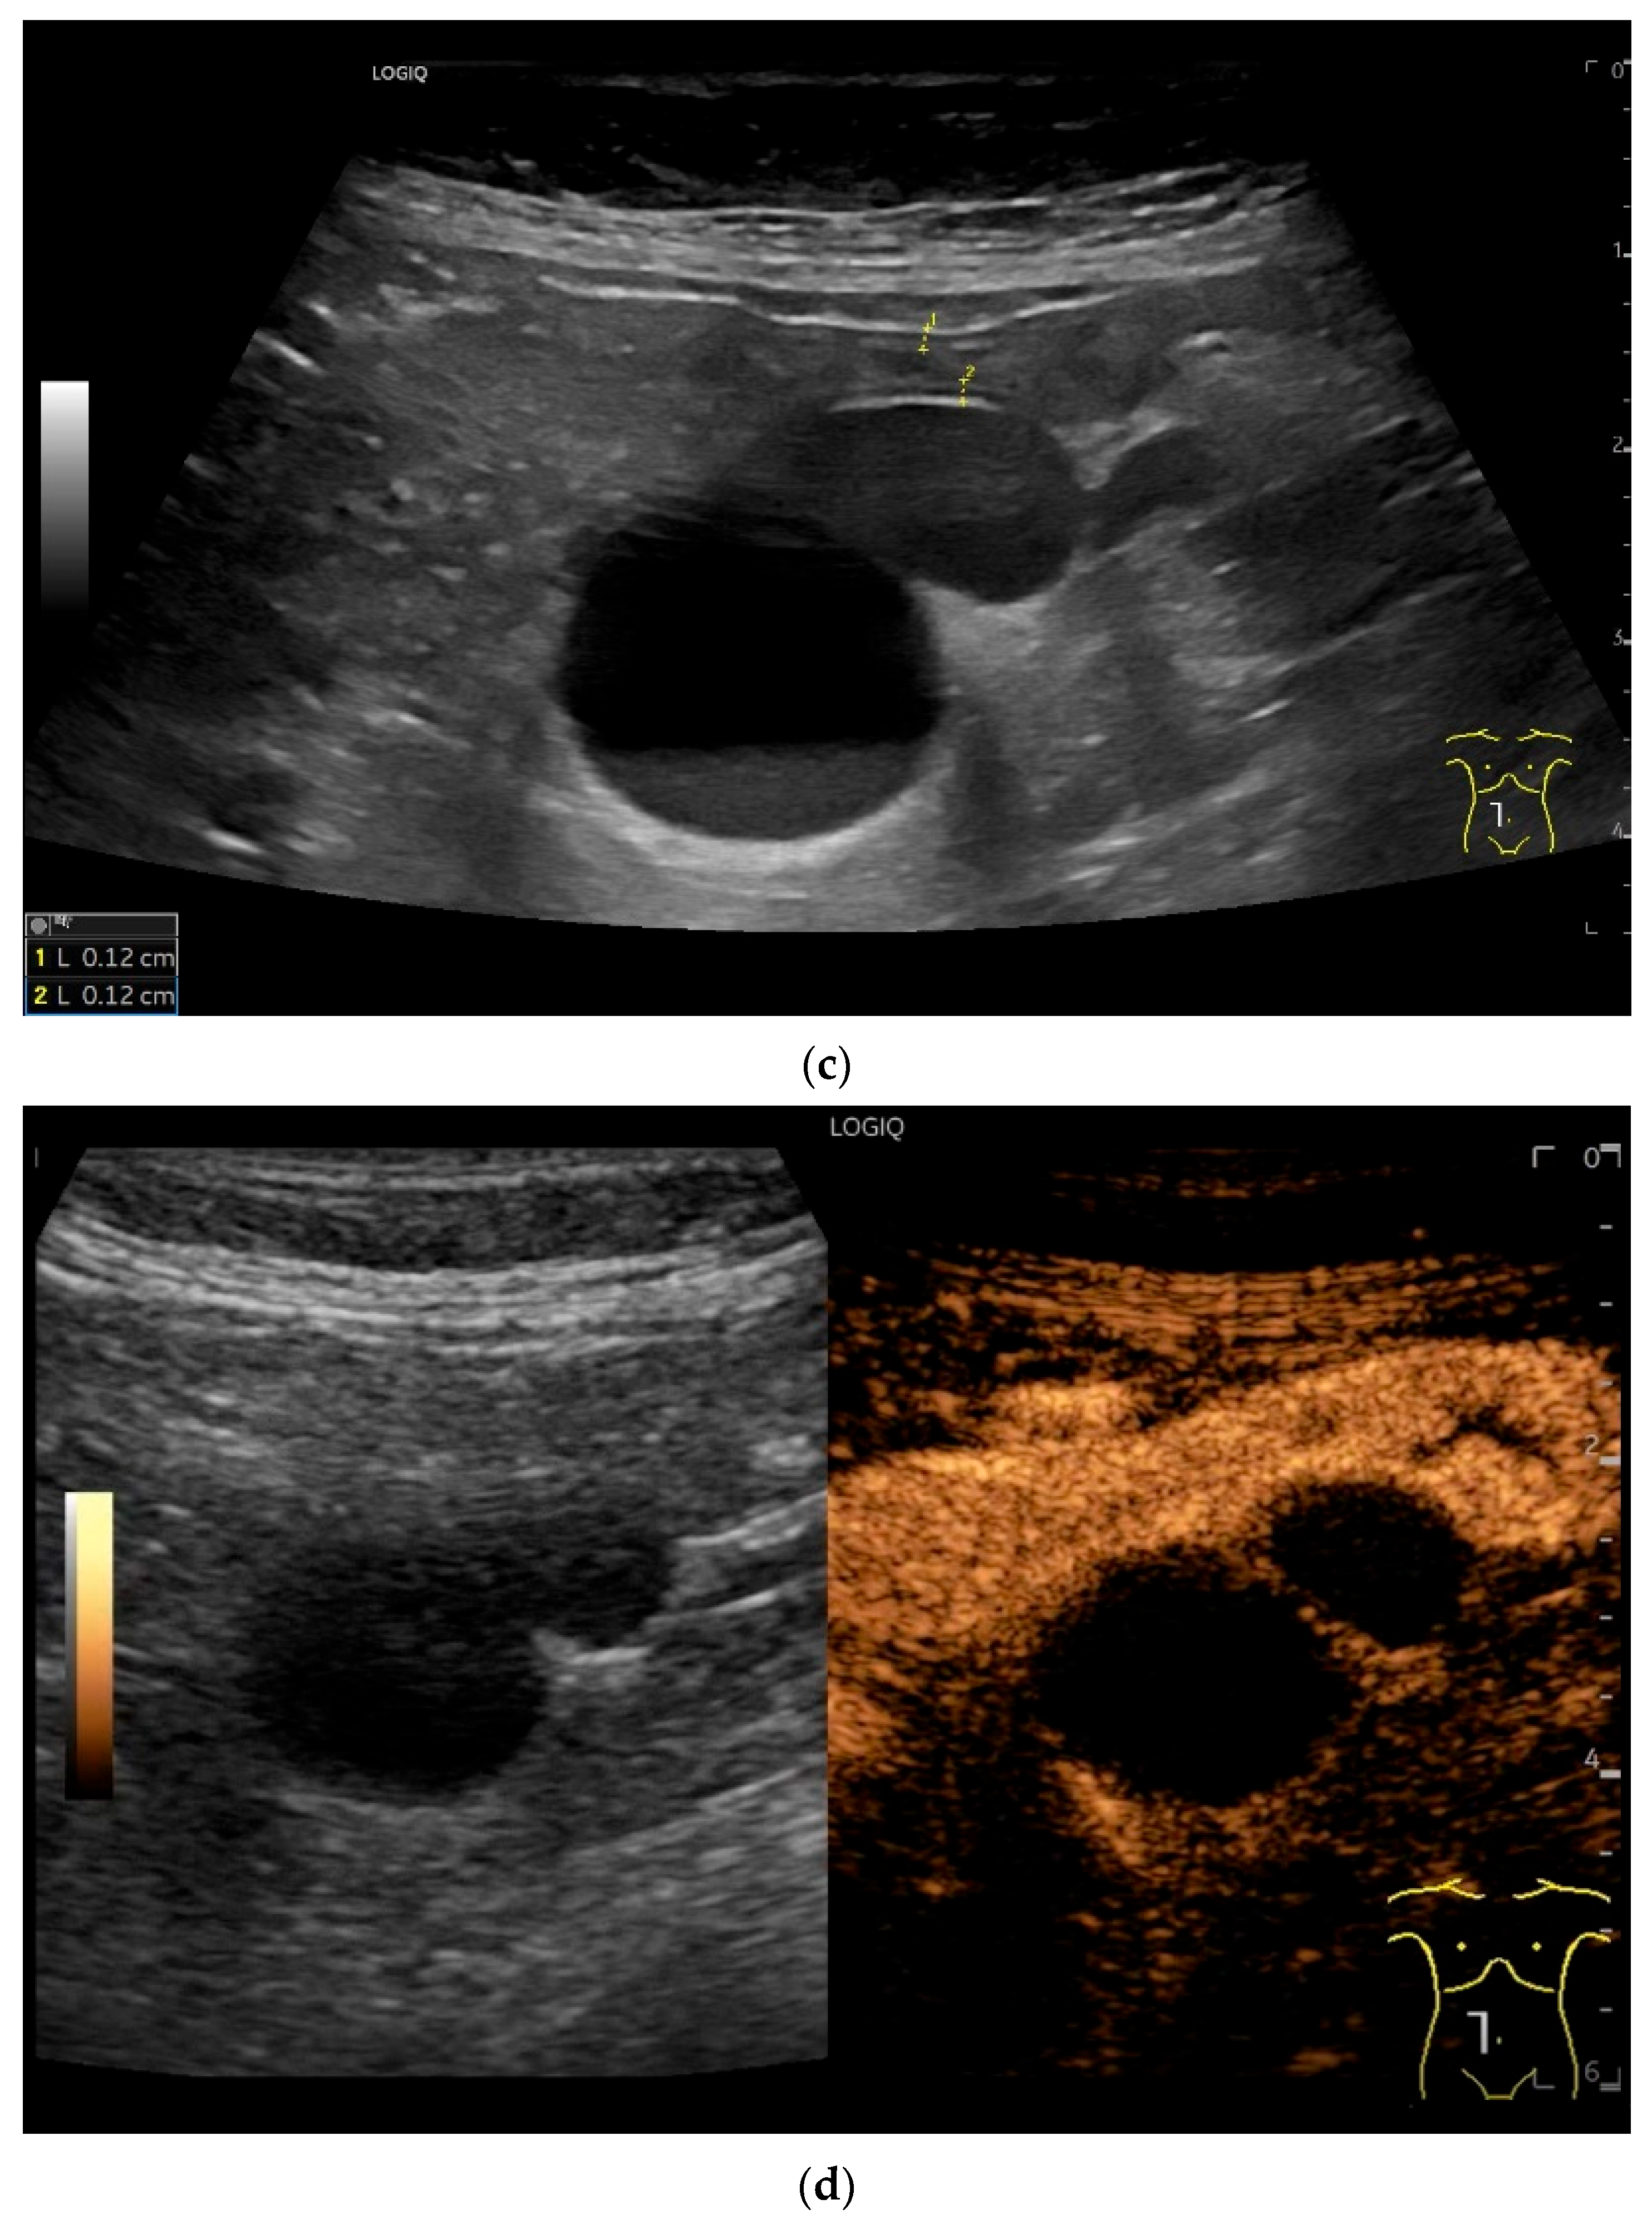

| Lymphoma | Very pronounced wall thickening with marked hypoechogenicity. Large regional and distant lymph nodes. Look for splenic infiltration. Tumor vessels on CDI and hyperenhancement on CEUS. Heterogeneous hyperechogenicity of the mesentery with walling of the mesenteric vessels. Multiple localizations are possible. |

- Cui, N.Y.; Gong, X.T.; Tian, Y.T.; Wang, Y.; Zhang, R.; Liu, M.J.; Han, J.; Wang, B.; Yang, D. Contrast-enhanced ultrasound imaging for intestinal lymphoma. World J. Gastroenterol. 2021, 27, 5438–5447. [Google Scholar] [CrossRef]